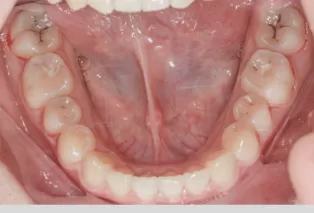

Intraoral photos after treatment